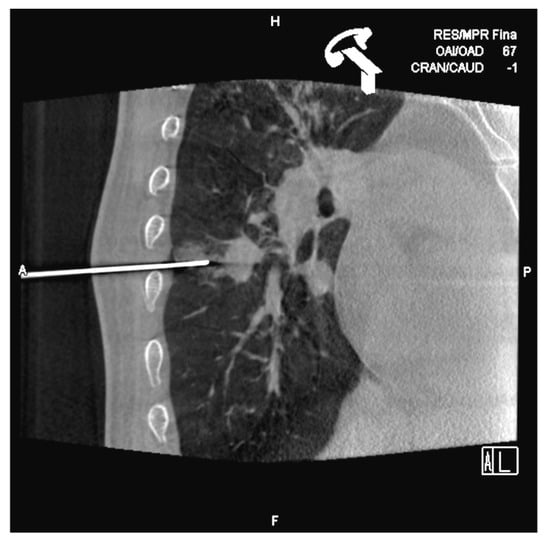

Cone-Beam CT-Guided Lung Biopsies: Results in 94 Patients

- Cone-Beam CT-guided biopsy is a highly accurate and safe technique with a sensitivity of 91.5% and a specificity of 100%.

- Risk factors for pneumothorax are a deeper location of the nodule and prone position of the patient in the procedure.